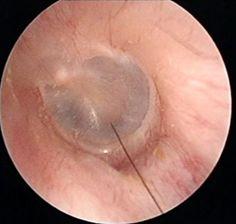

1. 好奇心驱使:我们都知道,耳朵是我们身体的一部分,但很少有机会看到耳朵内部的样子。医院吸耳屎视频的出现,满足了人们的好奇心,让大家得以一窥耳朵的“秘密”。